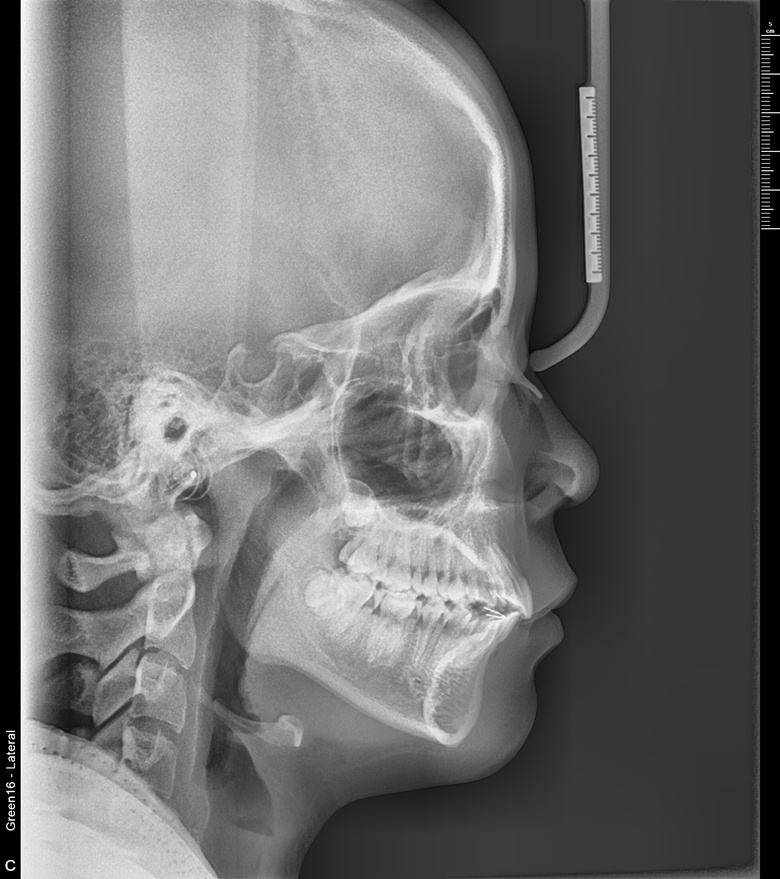

치료 전 사진입니다.